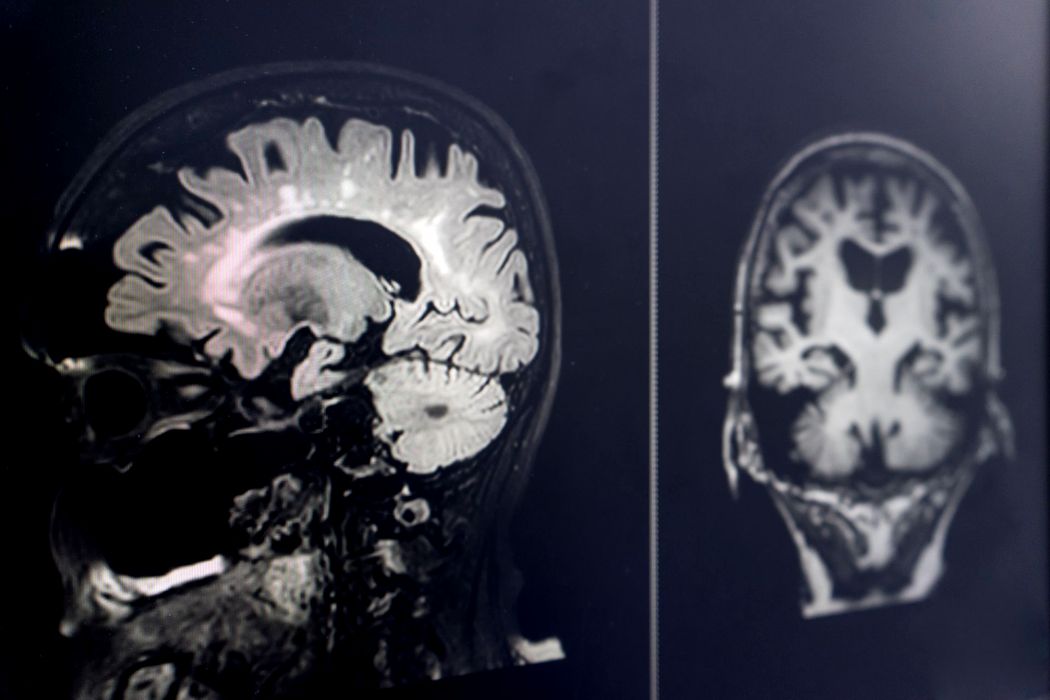

Oamenii de știință ar fi la un pas să rezolve un obstacol major în tratarea creierului

Una dintre cele mai mari provocări în livrarea tratamentelor pentru Alzheimer și alte boli legate de creier este depășirea sistemului robust de apărare pe care creierul îl are pentru a se proteja. Însă, datorită unui […]